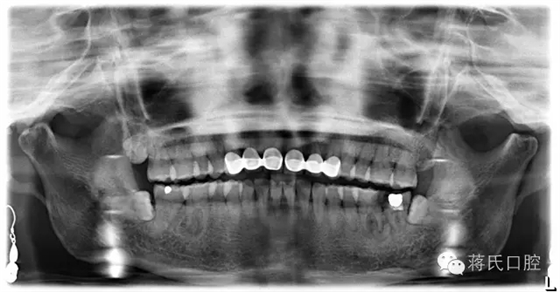

術(shù)前檢查:全景片顯示左下六七殘冠并發(fā)根尖炎癥,骨量豐滿、骨高度良好、但因為殘冠時間較長,對合牙伸長,咬合距離低,建議患者正畸治療上牙,但患者拒絕。因為患者是教師職業(yè)所以在設(shè)計方案及治療溝通中詳細(xì)醫(yī)囑,每次治療均經(jīng)過患者同意后操作。

種植前全景片